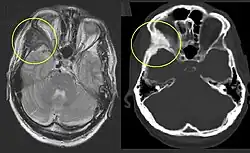

Die polyostotische FD ist klinisch und röntgenologisch auf den ersten Blick zu erkennen. Die befallenen Knochenbereiche weisen ein charakteristisches, milchglasartiges und unscharf begrenztes Erscheinungsbild im Röntgen oder CT auf. Eine Biopsie ist unnötig und erhöht die Bruchgefahr.